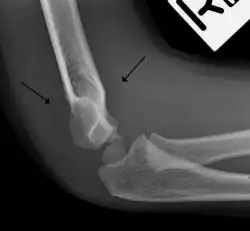

Fat pad sign

The fat pad sign, also known as the sail sign, is a potential finding on elbow radiography which suggests a fracture of one or more bones at the elbow. It may indicate an occult fracture that is not directly visible. Its name derives from the fact that it has the shape of a spinnaker (sail).[1] It is caused by displacement of the fat pad around the elbow joint. Both anterior and posterior fat pad signs exist, and both can be found on the same X-ray.

The fat pad sign is invaluable in assessing for the presence of an intra-articular fracture of the elbow. An anterior fat pad is often normal. However a posterior fat pad seen on a lateral x-ray of the elbow is always abnormal. The patient will be unable to flex their elbow and requires orthopaedic input.[2]